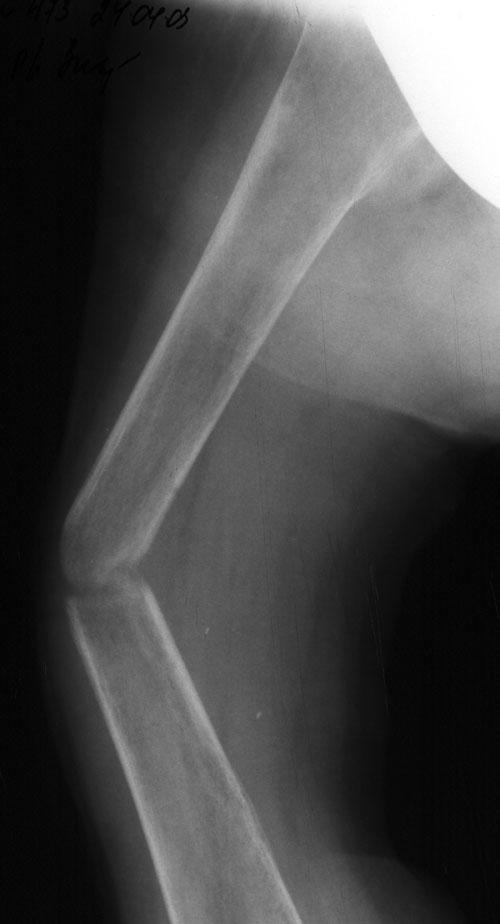

Выписка из амбулаторной карты пациента, 1980 г.р.Находится под наблюдением в поликлинике КНЦ РАН. Состоит на "Д" учёте по заболеваниям:Ювенильный идиопатический генерализованный остеопороз. Деформация грудной клетки за счёт множественных переломов грудины, рёбер. S-образный кифосколиоз грудного отдела позвоночника.Синдром гипофосфатемии неясного генеза. ВСД по кардиальному типу.Инвалид 1-й группы с детства. Последние 4 года не может передвигаться, возникают патологические переломы. Живёт в семье, материально-бытовые условия удовлетворительные.За последние 2 года состояние значительно ухудшилось - усилилась общая слабость, участились патологические переломы, которые не срастаются. Постоянно лежит в постели. Постоянный приём препаратов кальция и диеты с повышенным содержанием кальция, фосфора и белка эффекта не дают. С 11.07.2002 по 30.07.2002 г. лечился в травматологическом отделении АЦГБ с переломом костей правого предплечья со смещением. С 24.08.2002 по 08.09.2002 г. лечился в терапевтическом отделении по поводу острого бронхита с бронхоспастическим компонентом.На сегодняшний день статус. Состояние относительно удовлетворительное. В сознании. Положение вынужденное: сидя в инвалидном кресле, сам встать на ноги и передвигаться не может, туалет только с помощью родственников. Бледный, астеничный. Выраженная деформация грудной клетки, выраженный кифоз и сколиоз грудного отдела позвоночника. Экскурсия грудной клетки ограничена. Участие в акте дыхания вспомогательных межрёберных мышц. Пальпация грудной клетки безболезненна. Деформация всех крупных и мелких суставов за счёт увеличенных эпифизов. Деформация длинных трубчатых костей, мышцы рук и ног атрофичны. Температура - 36,8, ЧД - 29 в минуту. Дыхание жёсткое, проводится во все отделы. Слева от угла лопатки и в аксиллярной области влажные мелкопузырчатые хрипы, в межлопаточной области с обеих сторон свистящие хрипы. Пульс 90 ударов в минуту, ритмичный, симмитричный, слабого наполнения и напряжения. АД 120\80 мм рт. ст. Границы относительной сердечной тупости не расширены. Тоны сердца громкие, ритм правильный. Язык влажный, блестит. Живот при пальпации мягкий, не вздут, симметричный, участвует в акте дыхания, безболезненный. Печень по краю рёберной дуги. Стул регулярный, оформлен, без патологических примесей. Мочеиспускание свободное, безболезненное. Симптом Пастернацкого отрицателен с обеих сторон. Отёков нет.Анализ крови общий 26.08.2002: Hb-146 г\л, Эр.-4,8, ЦП-0,91, Лейк.-6,4, п.-4, с.-45, э.-5, м.-11, СОЭ-4 мм\ч.Анализ мочи общий 26.08.2002: Уд. вес-1025, белок-0,01, сахар-нет, лейк.-0-1 в поле зр., слизь+++, бактерии+.Анализ крови биохимический 26.08.2002: глюкоза-4,9, АЛТ-0,3, АСТ-0,5, биллирубин-11,9, креатинин-44,2, мочевина-3,8, СРБ (+).Анализ крови на микрореакцию - отрицательный.Флюрограмма за 2002: Резко выраженная деформация грудной клетки за счёт множественных переломов рёбер, грудины. Инфильтративных теней в лёгких не определяется. По сравнению с предыдущим исследованием от 01.12.2000 г. - ухудшение: нарастают деформация грудной клетки и позвоночника.ЭКГ за 2002 год: Синусовая тахикардия с ЧСС 88 в минуту. Отклонение ЭОС вправо. Признаки нарушения процессов реполяризации миокарда задней стенки левого желудочка. Повидимому, изменения ЭКГ обусловлены позиционными изменениями, возможно астеничным телосложением.Дополнительные методы исследования.Рентген правого предплечья (17.10.2002): Металлоостеосинтез по поводу перелома обеих костей правого предплечья в н\з: признаки репарации практически не определяются, сохраняется диастаз между отломками.Рентген правого предплечья (24.04.2003): Металлоостеосинтез по поводу перелома обеих костей правого предплечья в н\з: признаки репарации отсутствуют, формируются ложные суставы. Резко выраженный остеопороз.Рентген правого бедра (18.02.2003): Несросшийся перелом правого бедра на границе с\з и н\з со смещением отломков под углом открытым кнутри. Формирующийся ложный сустав. Выраженный остеопороз костей.Рентген правого бедра (24.04.2003): Угловое смещение отломков правого бедра увеличилось. Признаки репарации крайне вялые: по наружному краю отломков формируются замыкательные пластинки - ложный сустав. Выраженный остеопороз.